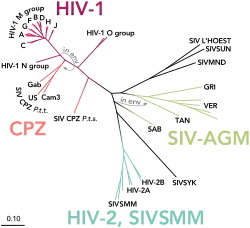

Es sind bisher zwei verschiedene Arten von HI-Viren bekannt, die als HIV-1 und HIV-2 bezeichnet werden. Die Homologie zwischen HIV-1 und HIV-2 beträgt auf Aminosäuresequenzebene nur etwa 45 bis 50 Prozent. Hierbei sind etwa 95 % der Infektionen auf HIV-1 zurückzuführen.[47] HIV-1 und HIV-2 können weiter in Gruppen unterteilt werden, die teilweise mit unterschiedlicher Häufigkeit in verschiedenen Regionen der Welt auftreten.

So ist HIV-1 in vier Gruppen unterteilt, die mit M, N, O und P bezeichnet werden.[47][48]

- M steht für engl. major group ‚Hauptgruppe‘ und ist am häufigsten verbreitet. Sie wird ferner in verschiedene Subtypen unterteilt, die mit A, B, C, D, F, G, H, J, K und L[49] bezeichnet werden. Etwa 70 % der HIV-1-Infektionen geht auf die Subtypen A, B und C zurück; Subtyp B kommt vor allem in Nordamerika und Europa vor, A in Osteuropa und C hauptsächlich in Südafrika und Asien. In Mitteleuropa wie Deutschland ist der Subtyp B aus der Gruppe M von HIV-1 am häufigsten, besonders unter MSM und injizierenden Drogenkonsumenten.

- Die O-Gruppe wurde nach outlier ‚Sonderfall‘ benannt. Infektionen sind weitestgehend auf Westafrika (Kamerun) beschränkt.[48] Sie stammt ursprünglich aus Gorillas (SIVgor).[50]

- N der Gruppe N steht für „non-M“ und „non-O“ und bislang nur bei einigen wenigen Menschen nachgewiesen.[50]

- Ferner wurde Gruppe P eingeführt, es wurde ebenfalls in sehr wenigen Menschen nachgewiesen.[51]

Eine Koinfektion mit verschiedenen Subtypen kann dazu führen, dass zirkulierende rekombinante Formen entstehen, die circulating recombinant forms (CRFs) genannt werden.[51][52] Die Reihenfolge der Entdeckung wird durch eine sequenzielle Nummer kenntlich gemacht, die enthaltenen Subtypen durch entsprechende Buchstaben. So ist zum Beispiel CRF01_AB die erste identifizierte CRF (01) mit der Rekombination der Subtypen A und B. Falls mehr als zwei Subtypen präsent sind, wird dies durch cpx (complex) kenntlich gemacht, z. B. CRF06_cpx – sie enthält die Subtypen A, G, J und K. Es wurden über 100 CRFs identifiziert.[53] Die Klassifikation der HIV-Stämme ist entsprechend komplex und noch nicht abgeschlossen.

HIV-1, das insgesamt häufiger ist, und HIV-2 ähneln sich prinzipiell hinsichtlich des klinischen Infektionsverlaufs und der krankmachenden (pathogenen) Eigenschaften, auch wenn die Infektion mit HIV-2 wohl insgesamt langsamer verläuft. Die beiden Stämme sehen unter dem Elektronenmikroskop gleich aus, unterscheiden sich jedoch in der molaren Masse der Proteine und in der Anordnung und Nukleotidsequenz der Gene. HIV-1 und HIV-2 entstanden aus unterschiedlichen Typen der bei bestimmten Affenarten vorkommenden SI-Viren. HIV-2 wurde überwiegend in Westafrika nachgewiesen.[48]

HIV-1 wurde ursprünglich von SIV-infizierten Schimpansen und Gorillas auf den Menschen übertragen. So konnte für die Gruppen M und N nachgewiesen werden, dass sie aus Schimpansen stammen, während HIV-1 P von Gorillas auf den Menschen übertragen wurde.[54] Alle vier HIV-1-Gruppen (M, N, O und P) sind auf vier unabhängige Zoonosen (d. h. Tier-zu-Mensch-Übertragungen) zurückzuführen, wobei bislang nur die Gruppe M die Ausmaße einer Pandemie angenommen hat.[55][56] Der Grund für die höhere Infektiosität des HIV-1-M-Stammes beruht unter anderem auf spezifischen Eigenschaften des Virusproteins vpu der M-Gruppe, mit deren Hilfe gleich zwei Infektionsbarrieren überwunden werden: Zum einen wird der antivirale Faktor Tetherin auf humanen Zellen effektiv ausgeschaltet und zum anderen wird der CD4-Rezeptor abgebaut.[55][57][58]